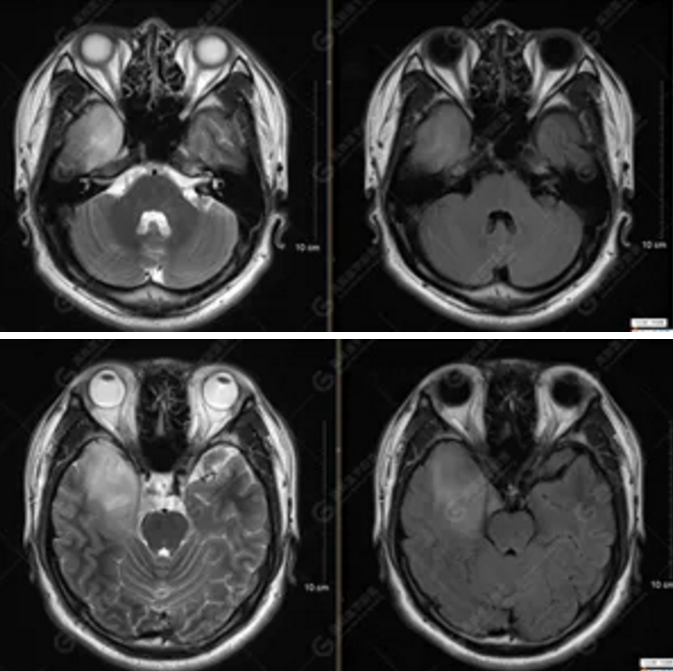

MR影像圖

【MRI平掃及增強(qiáng)檢查所見(jiàn)】右側(cè)額顳島葉、右側(cè)海馬及右側(cè)基底節(jié)區(qū)見(jiàn)一團(tuán)塊狀異常信號(hào)影,累及右側(cè)下丘腦及視交叉,大小約5.1cm×4.5cm×4.3cm,呈長(zhǎng)T1長(zhǎng)T2信號(hào),F(xiàn)LAIR序列呈等、稍高信號(hào),DWI序列呈稍高信號(hào),ADC圖高信號(hào),增強(qiáng)后無(wú)明顯強(qiáng)化;病灶周?chē)?jiàn)片狀長(zhǎng)T1長(zhǎng)T2水腫信號(hào)影,F(xiàn)LAIR序列呈高信號(hào),病灶內(nèi)見(jiàn)右側(cè)大腦中動(dòng)脈穿行。余腦實(shí)質(zhì)內(nèi)未見(jiàn)局灶性信號(hào)異常,增強(qiáng)后未見(jiàn)異常強(qiáng)化。右側(cè)側(cè)腦室輕度受壓,余腦室、腦池大小、形態(tài)均正常,中線(xiàn)結(jié)構(gòu)居中